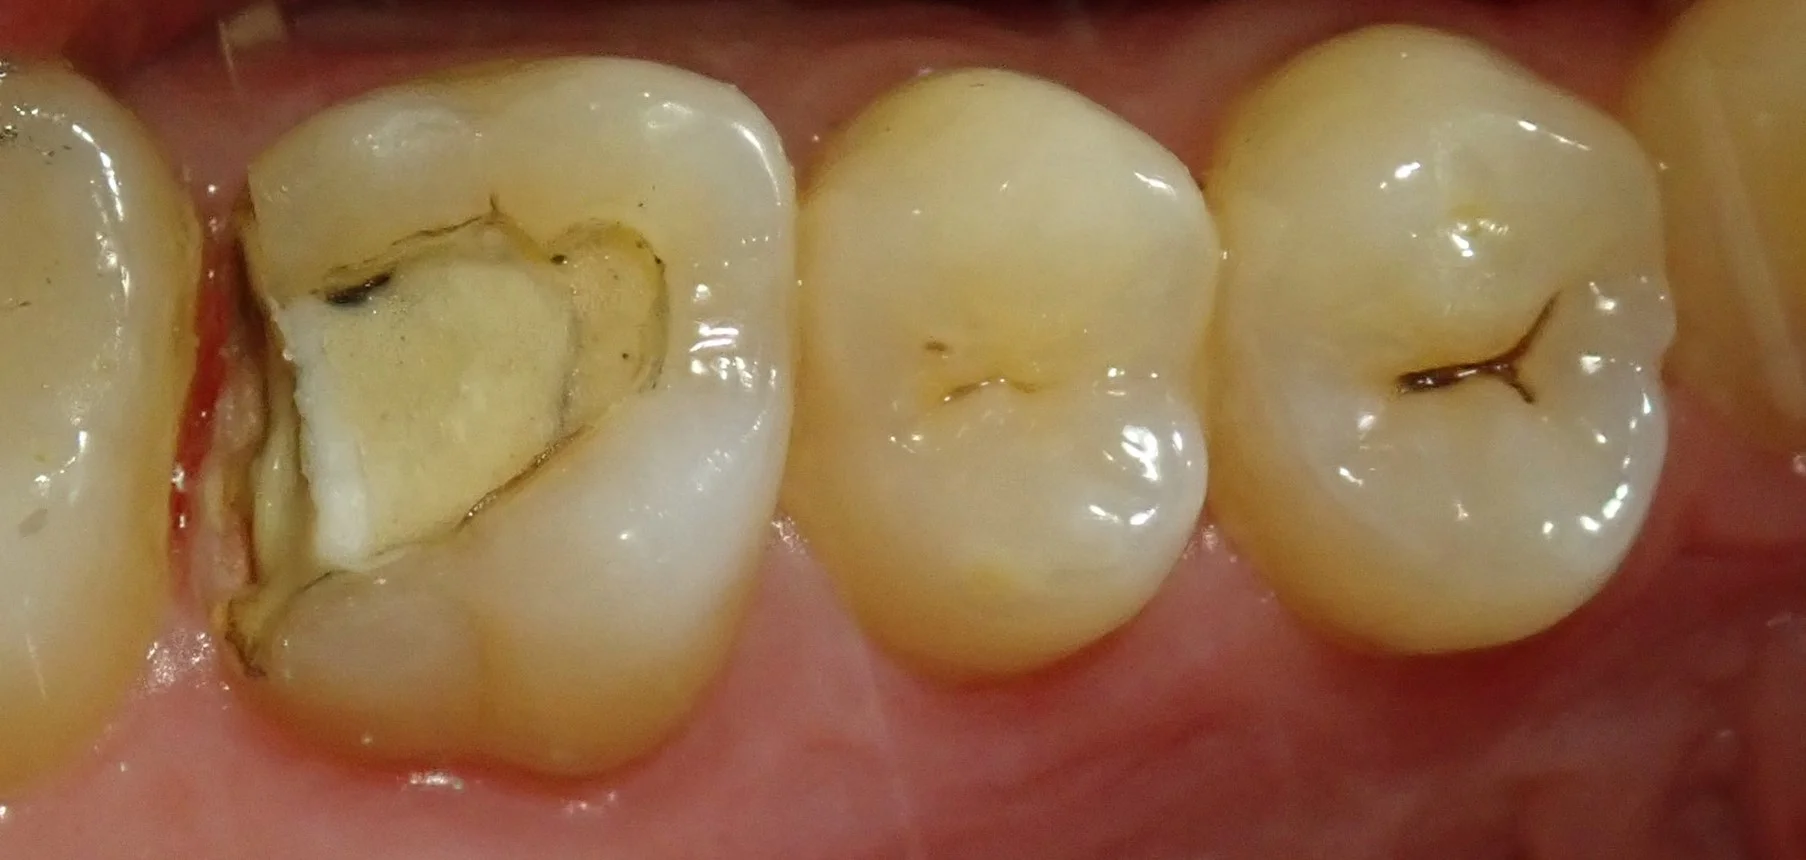

金属のみを除去したのがこの写真です。

歯と金属の間に入っているセメント部分がなくなっていたため、そこに細菌繁殖が起こり、歯茎に炎症が生じてしまっています。

また、金属の下に入っている白い部分の下にも虫歯が広がってしまっている状況でした。